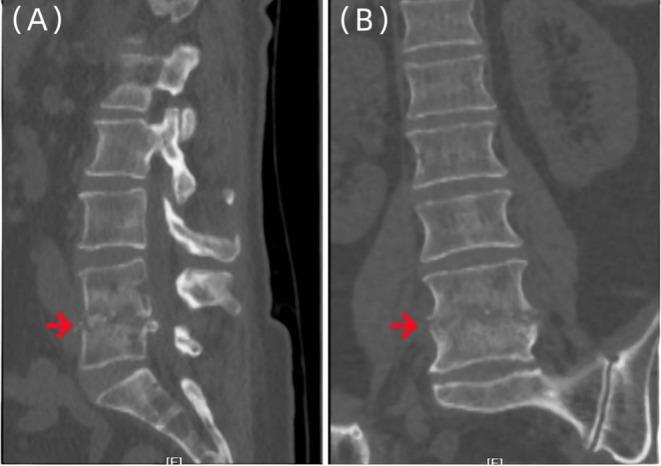

Suppurative Spondylitis Misdiagnosed as Endplate Inflammation: A Rare Case Report.

Spinal infectious diseases are difficult to diagnose and treat; we reported a case of pyogenic spondylitis misdiagnosed as terminal discitis and successfully treated. The application of metagenomic next-generation sequencing technology holds promise in greatly improving diagnostic efficiency.